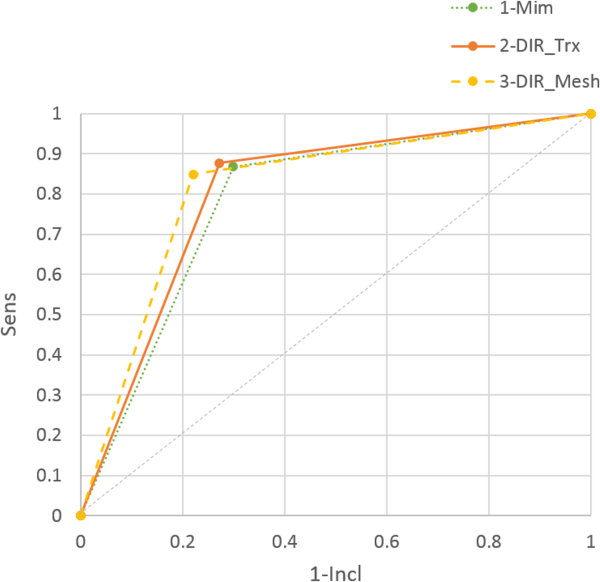

In Figure 4, the modified ROC curve is shown; as already reported in Table 3, DIR_Mesh performed slightly better than the other 2 methods, having an area under the curve higher than the others, although nonsignificant (P value = .26).

Figure 4

Modified receiver operating characteristic (ROC) curve for the 3 methods.